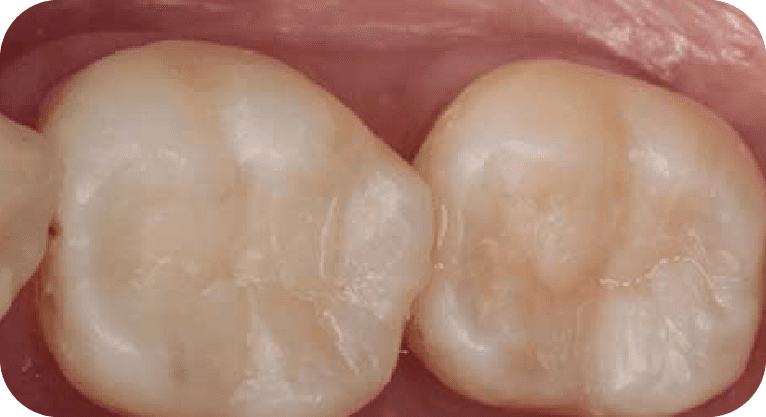

Paciente masculino, “25” años

Tratamiento: Tratamiento de conducto

El paciente presentaba dolor en dos molares por caries profundas. Se realizó endodoncia en ambas piezas, desinfectando y sellando los conductos, seguido de coronas de zirconio para restaurar su función.